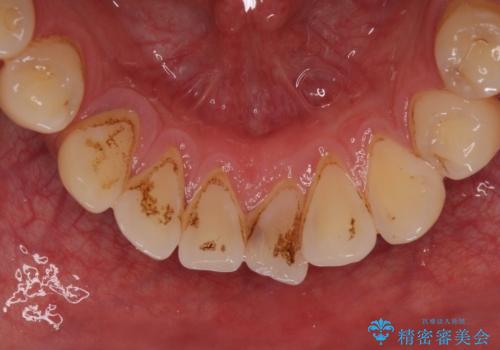

- 前歯や奥歯の虫歯を放置しており、それらの治療を契機に真っ白な歯にしたいとのことで来院された患者様です。

咬み合わせを改善するに当たって、抜歯しなければならない歯や歯列の改善が必要な箇所があったため、矯正治療やインプラント治療から始めていくこととしました。

不自然なくらい真っ白にしたいとのことでしたので、透明感のないフルジルコニアクラウンを用いて補綴することとしました。